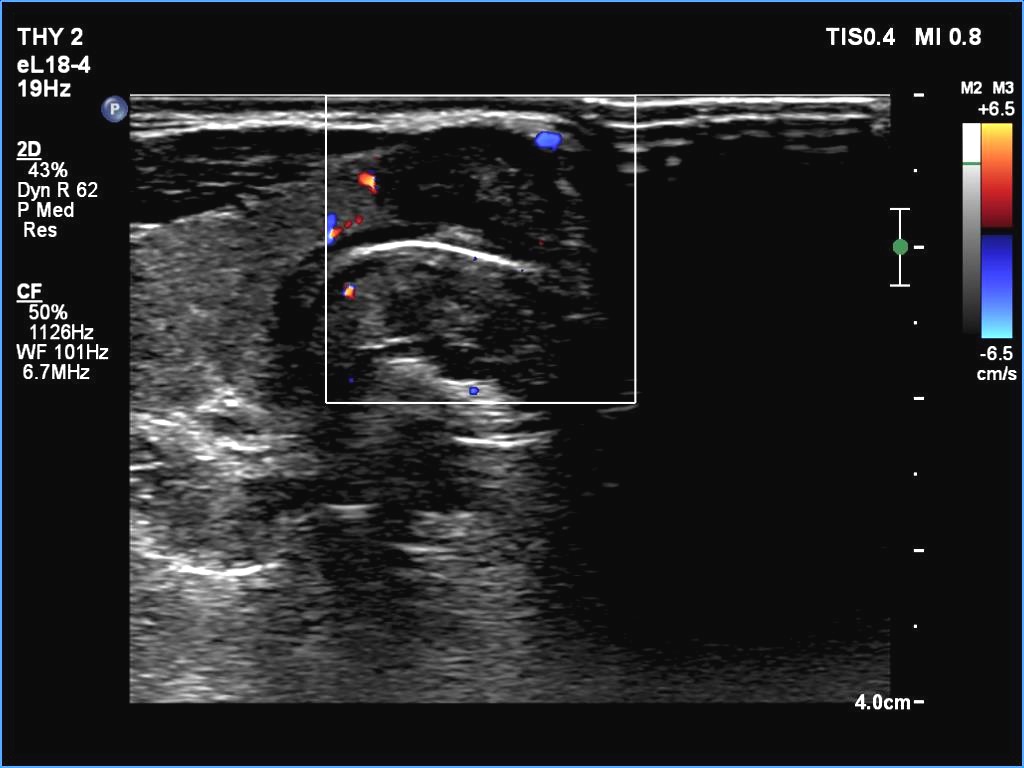

Isthmus, transverse scan, color Doppler mode. The vascularity is scanty.